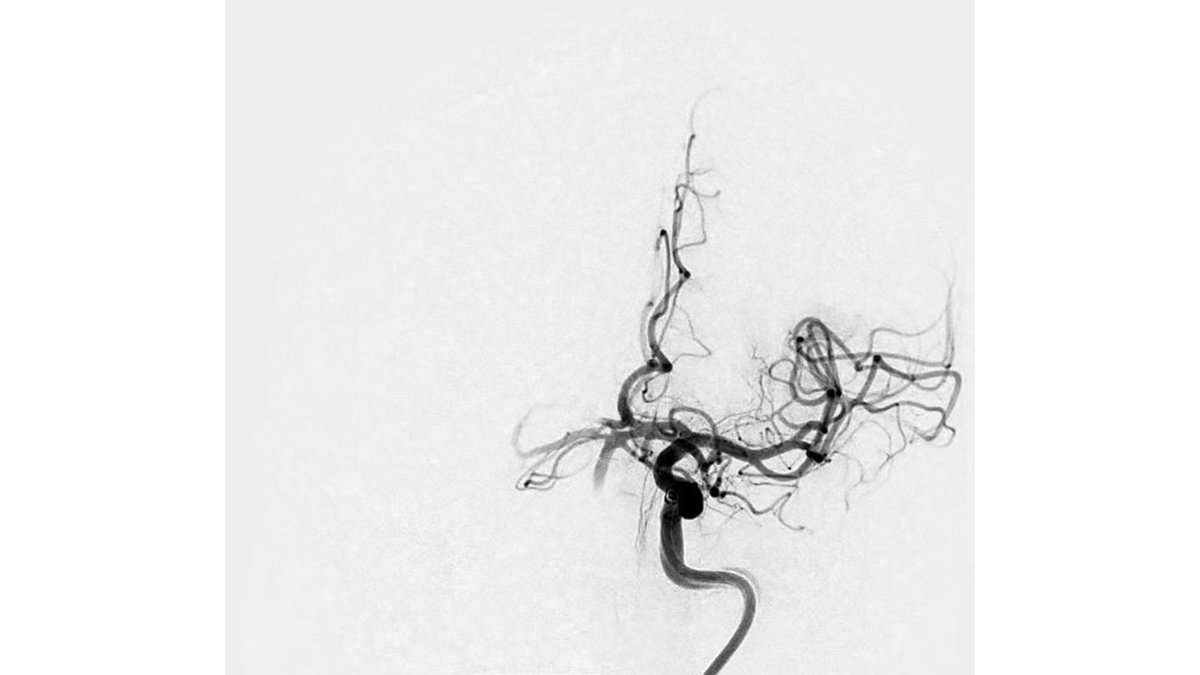

Thank you to Dr. Wei-Chiang, Chen out of #CMUH, #Taiwan🇹🇼, for sharing these great images from a first case using #RED43 in Left M2. Fantastic first pass and final TICI3 result. @PenNeuro